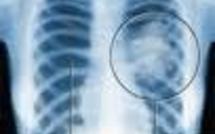

Santé

L'information médicale